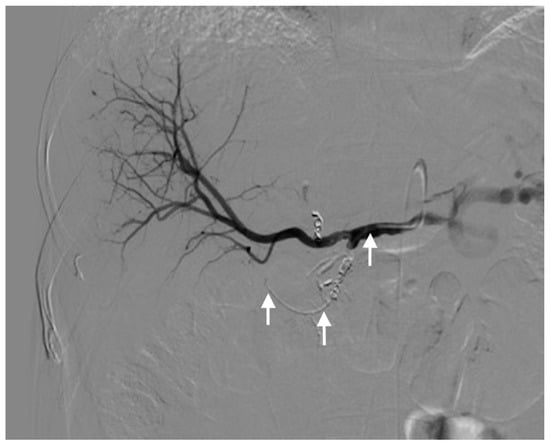

| Extrahepatic perfusion | 13 (30.2) | 8/6 | 5/3 |